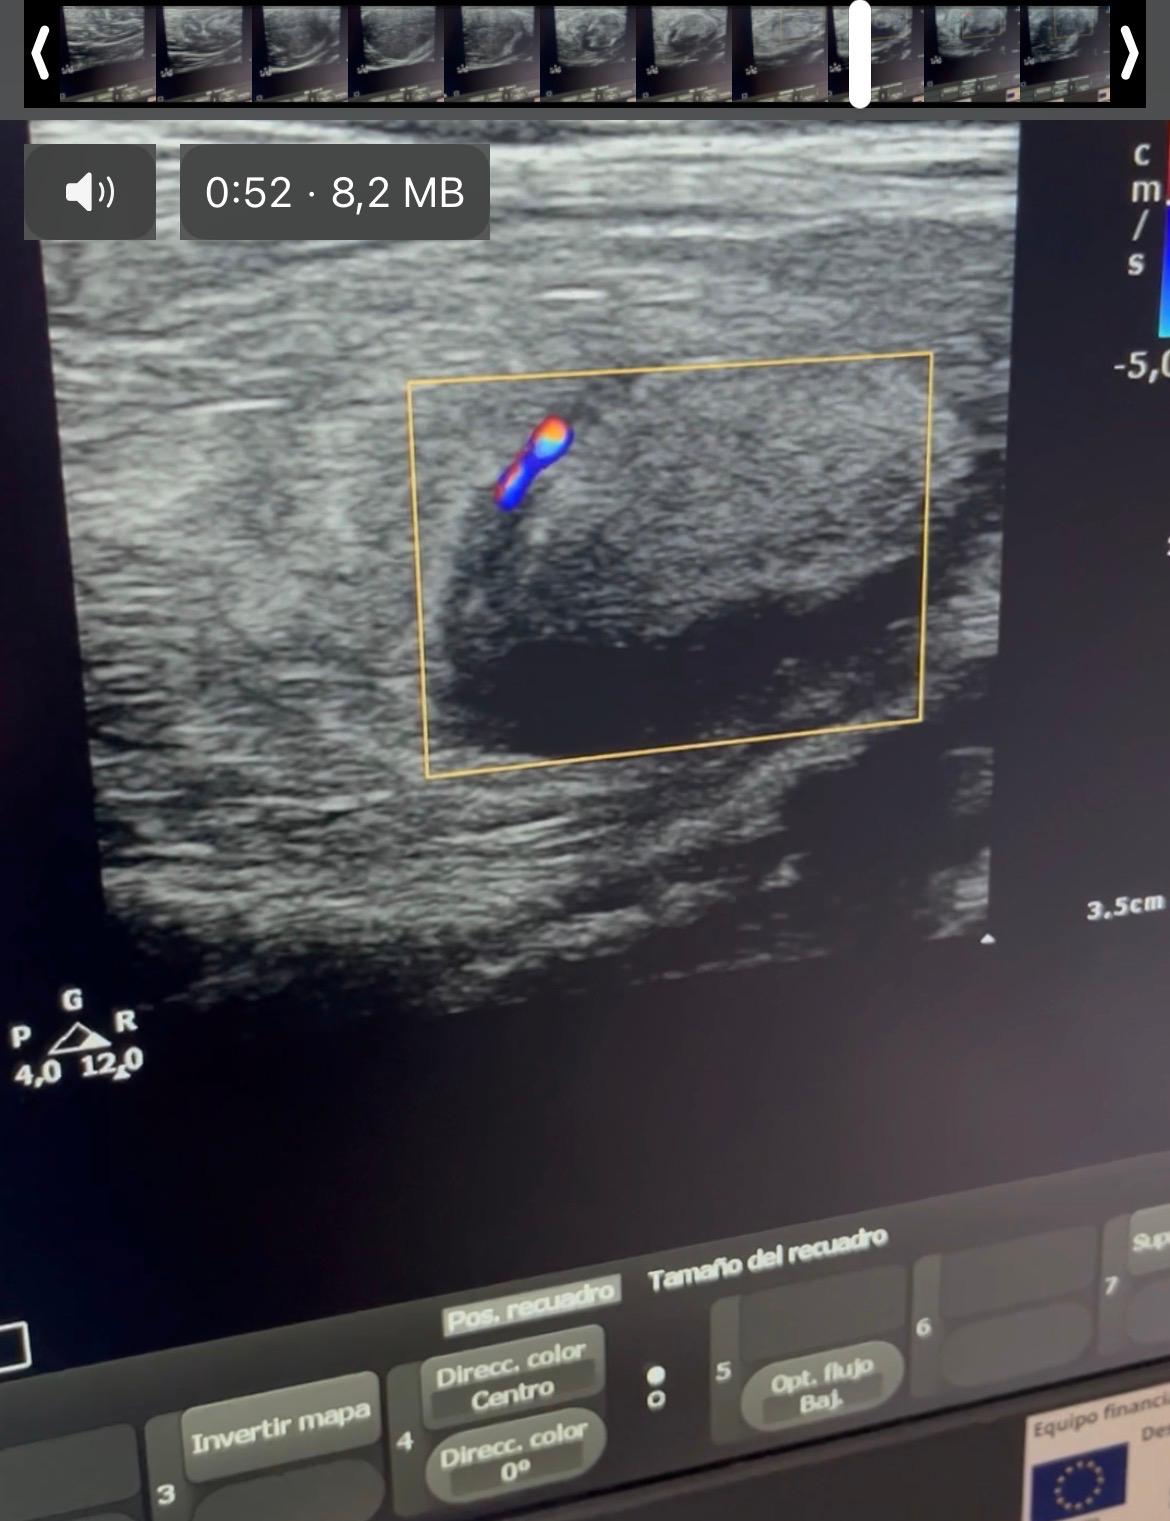

Hallazgos ecográficos

Ecografía clínica con sonda lineal: lesión mal definida, heterogénea, con áreas hiperecogénicas e hipoecoicas, vascularizada, de aproximadamente 5x7cm, sospechosa de malignidad.